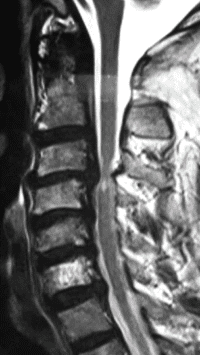

Based on these tests, or sometimes, in the presence of some significant signs or symptoms, you may be asked to undergo MRI scanning. Plain x-rays demonstrate bony features; while MRI demonstrates the spinal cord, its nerve roots, the intervertebral disc between the two bones of the spine. Both these tests are complimentary in nature; doing one does not necessarily mean that the other one is not needed.